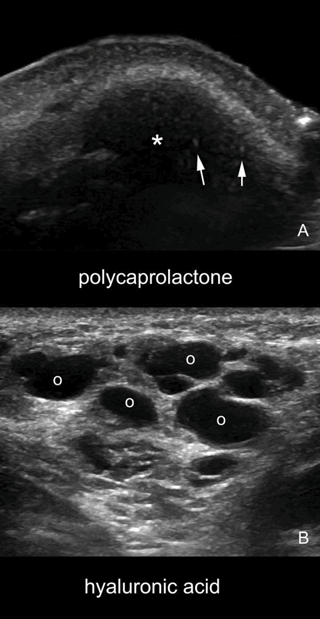

Non-surgical rhinoplasty with hyaluronic acid (HA) fillers is becoming very popular as a temporary way of improving the aesthetics and balance of the nose (Figure 1 and Figure 2).

Figure 1: A comparison sonogram between PCL and HA. The HA produces multiple anechoic pseudocystic structures (B). The bright hyperechoic spots noticed in PCL represent microspheres with collagen stimulating properties (A).

This product is composed of microspheres of a totally bioresorbable polymer, polycaprolactone (PCL) (30%), and is in an aqueous carboxymethyl cellulose (CMC) (70%) gel carrier.

The CMC gel carrier has an immediate volumising effect and is gradually resorbed by macrophages in six to eight weeks, the PCL microspheres stimulate neocollagenesis. Rhinoplasty surgery, if necessary is planned for three months after the treatment. It is the authors’ impression that following PCL injections, the nasal soft tissue envelope is more resistant during surgery.